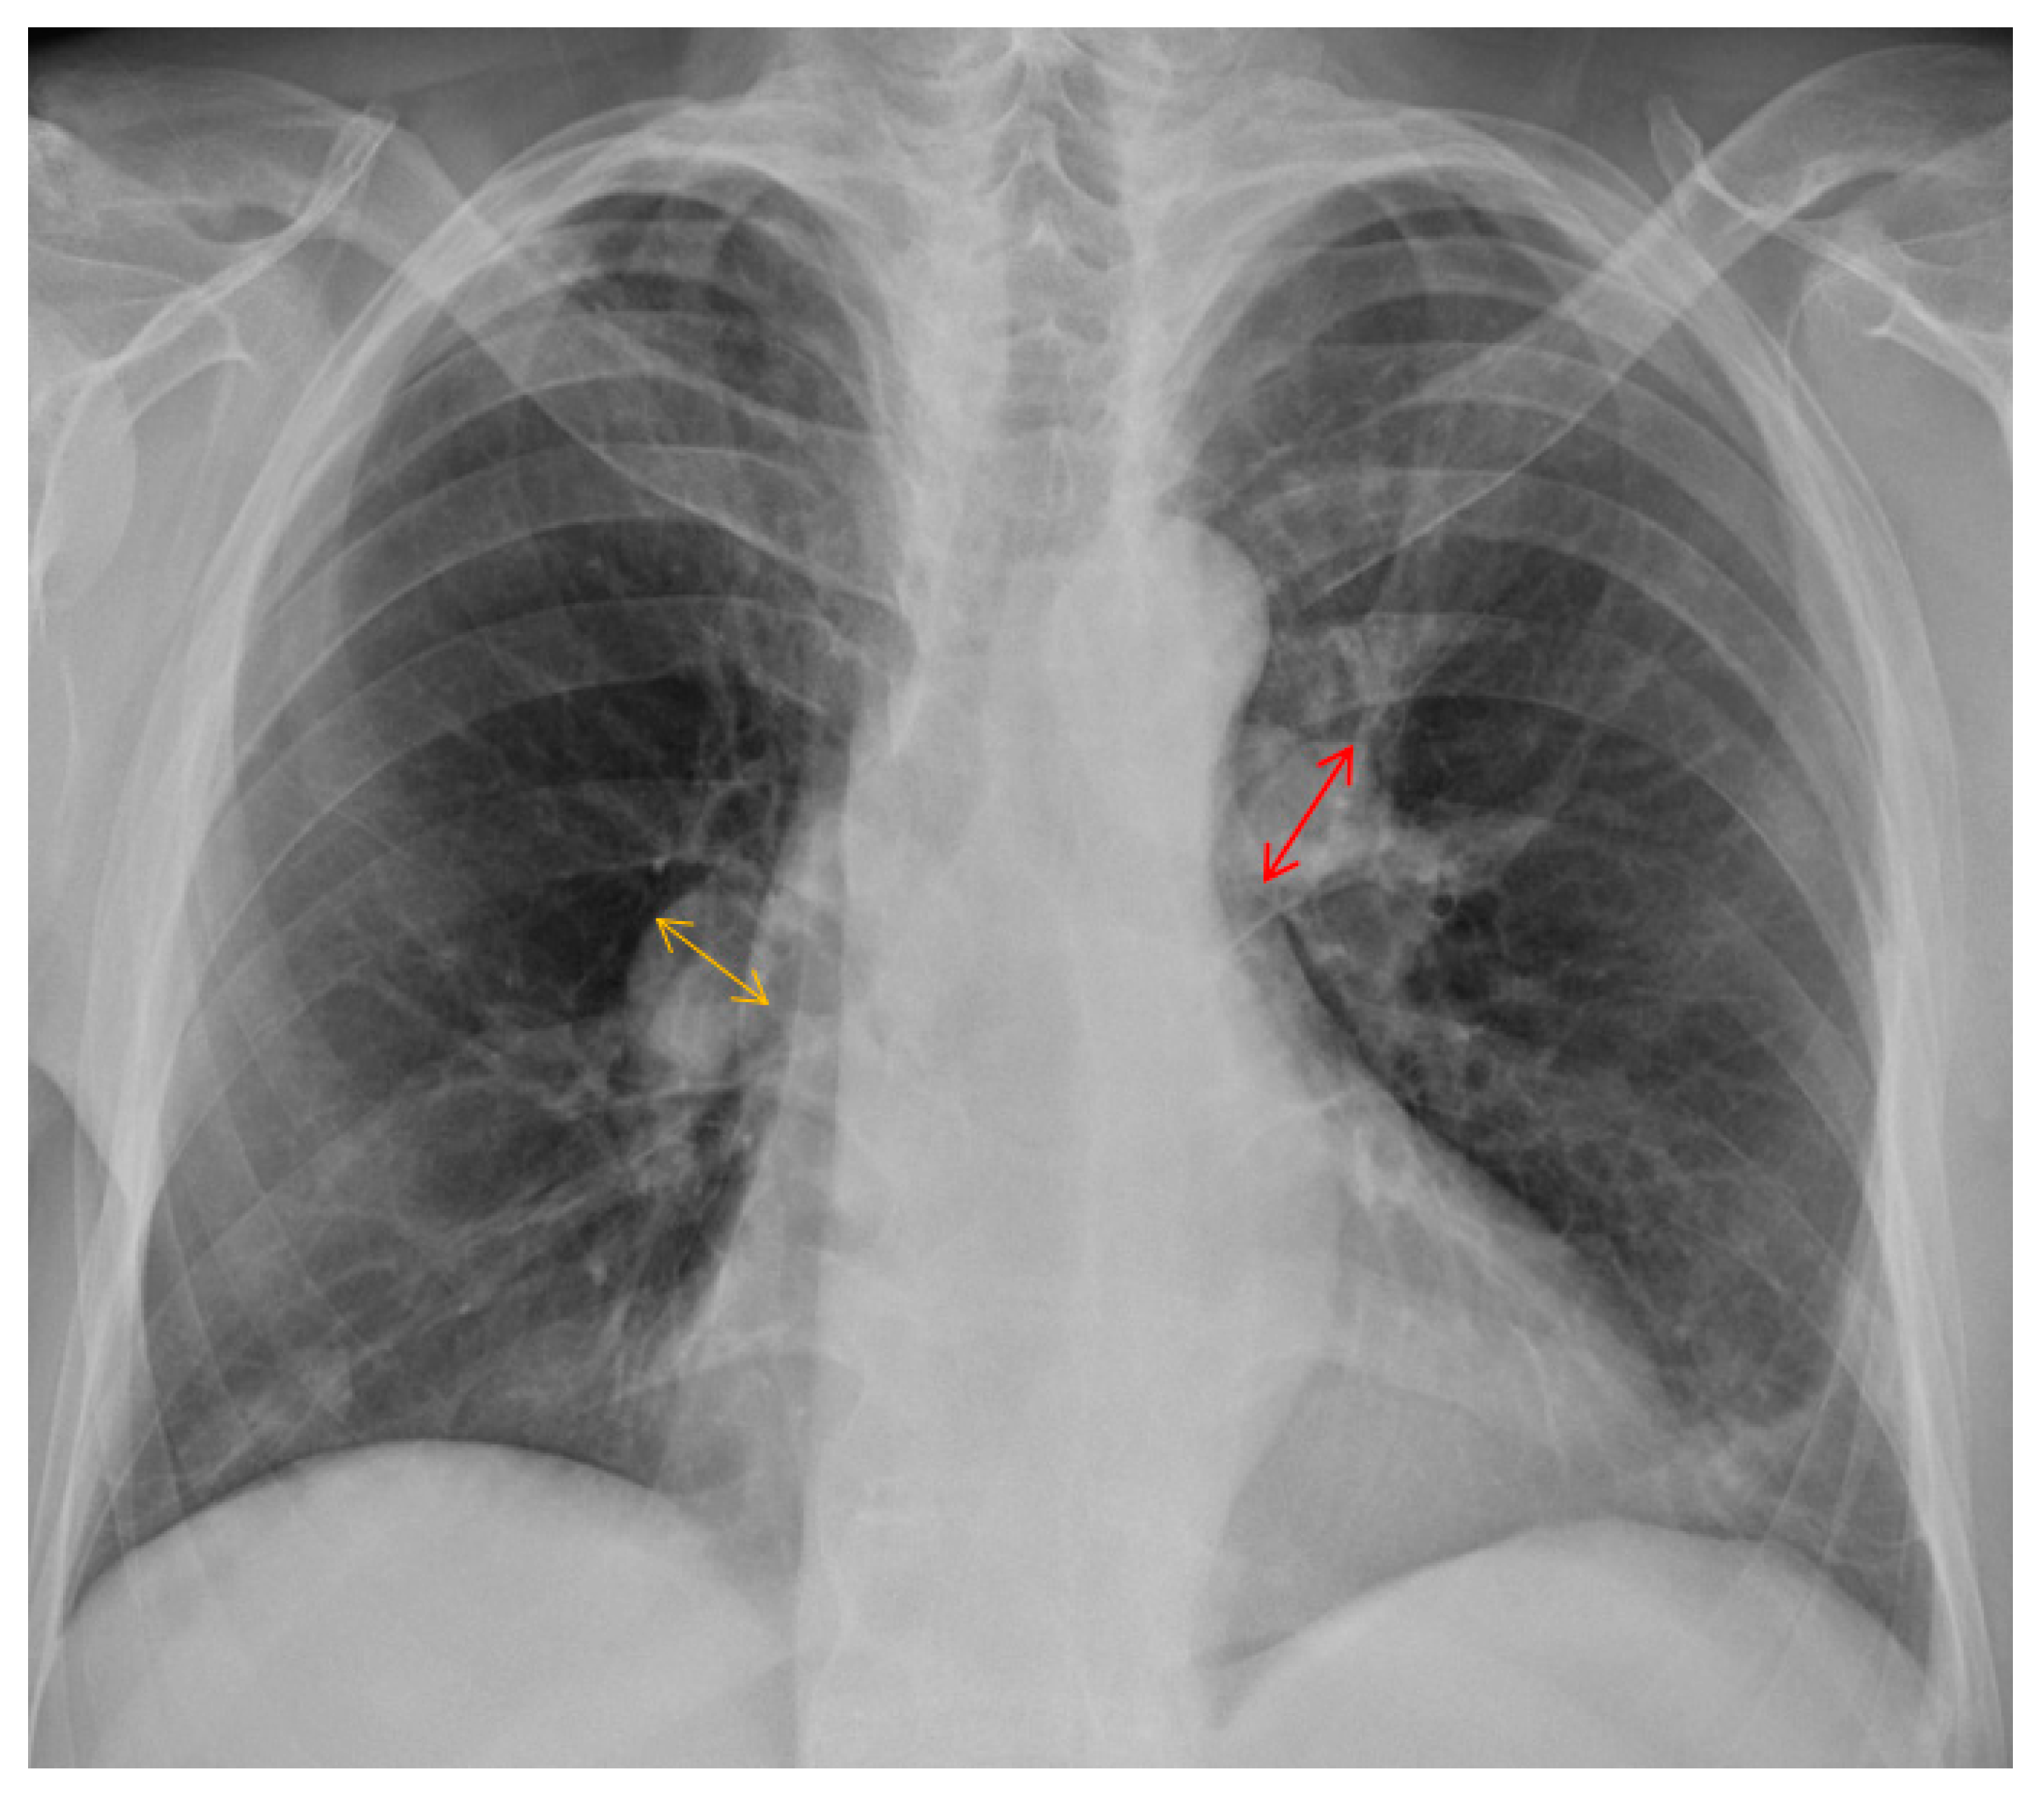

2. Case Presentation